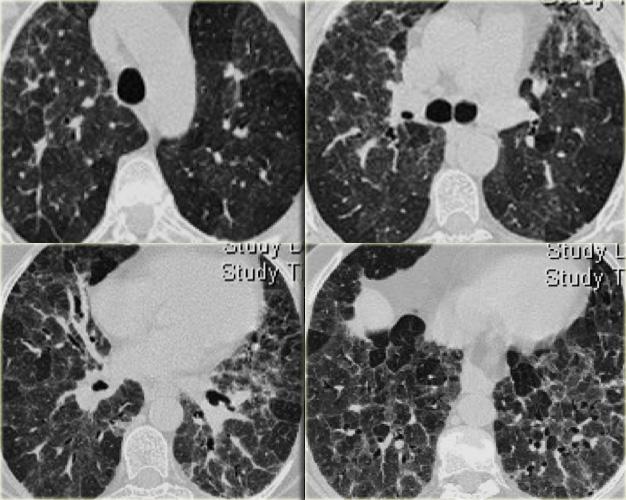

Bệnh nhân này nhập viện với triệu chứng khó thở cấp tính và phim X-quang ngực bình thường (không trình bày).

HRCT lúc nhập viện (trái) cho thấy các vùng kính mờ theo phân bố tiểu thùy.

HRCT kiểm tra mười ngày sau (phải) cho thấy các tổn thương đã thoái lui hoàn toàn mà không cần điều trị.

Các tổn thương được cho là do viêm phổi quá mẫn.